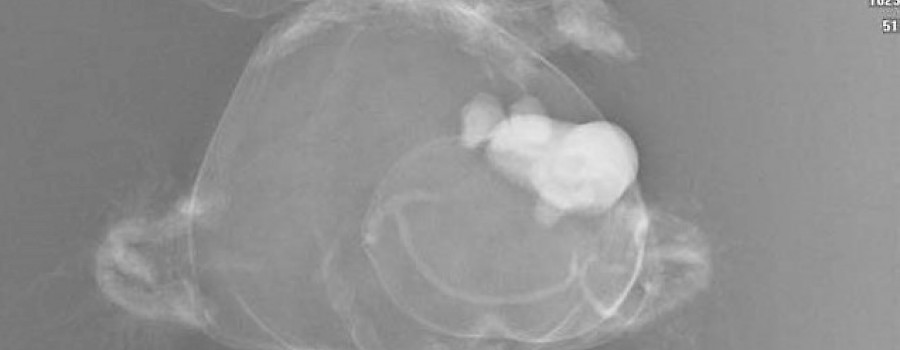

In Deutschland passieren jährlich etwa 13 600 Schulterluxationen. Der Anteil dorsaler Schulterluxationen beträgt dabei lediglich 1,7 bis 7 Prozent. Die hintere Luxation ist meist Folge indirekter Gewalteinwirkung, etwa bei generalisierten Muskelkrämpfen.

Heute wird einem ein solcher Fall wohl nicht mehr begegnen, aber in der zweiten Hälfte des letzten Jahrhunderts wurde das schon das eine oder andere Mal beobachtet.